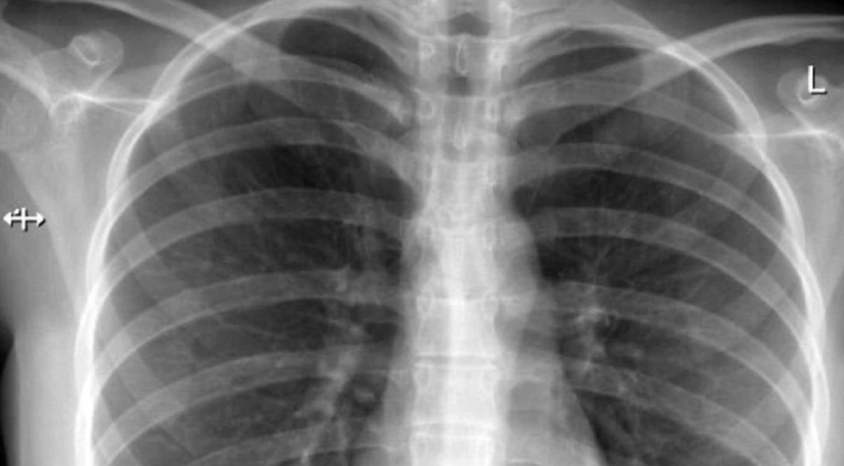

• Pneumonie (Lungenentzündung)